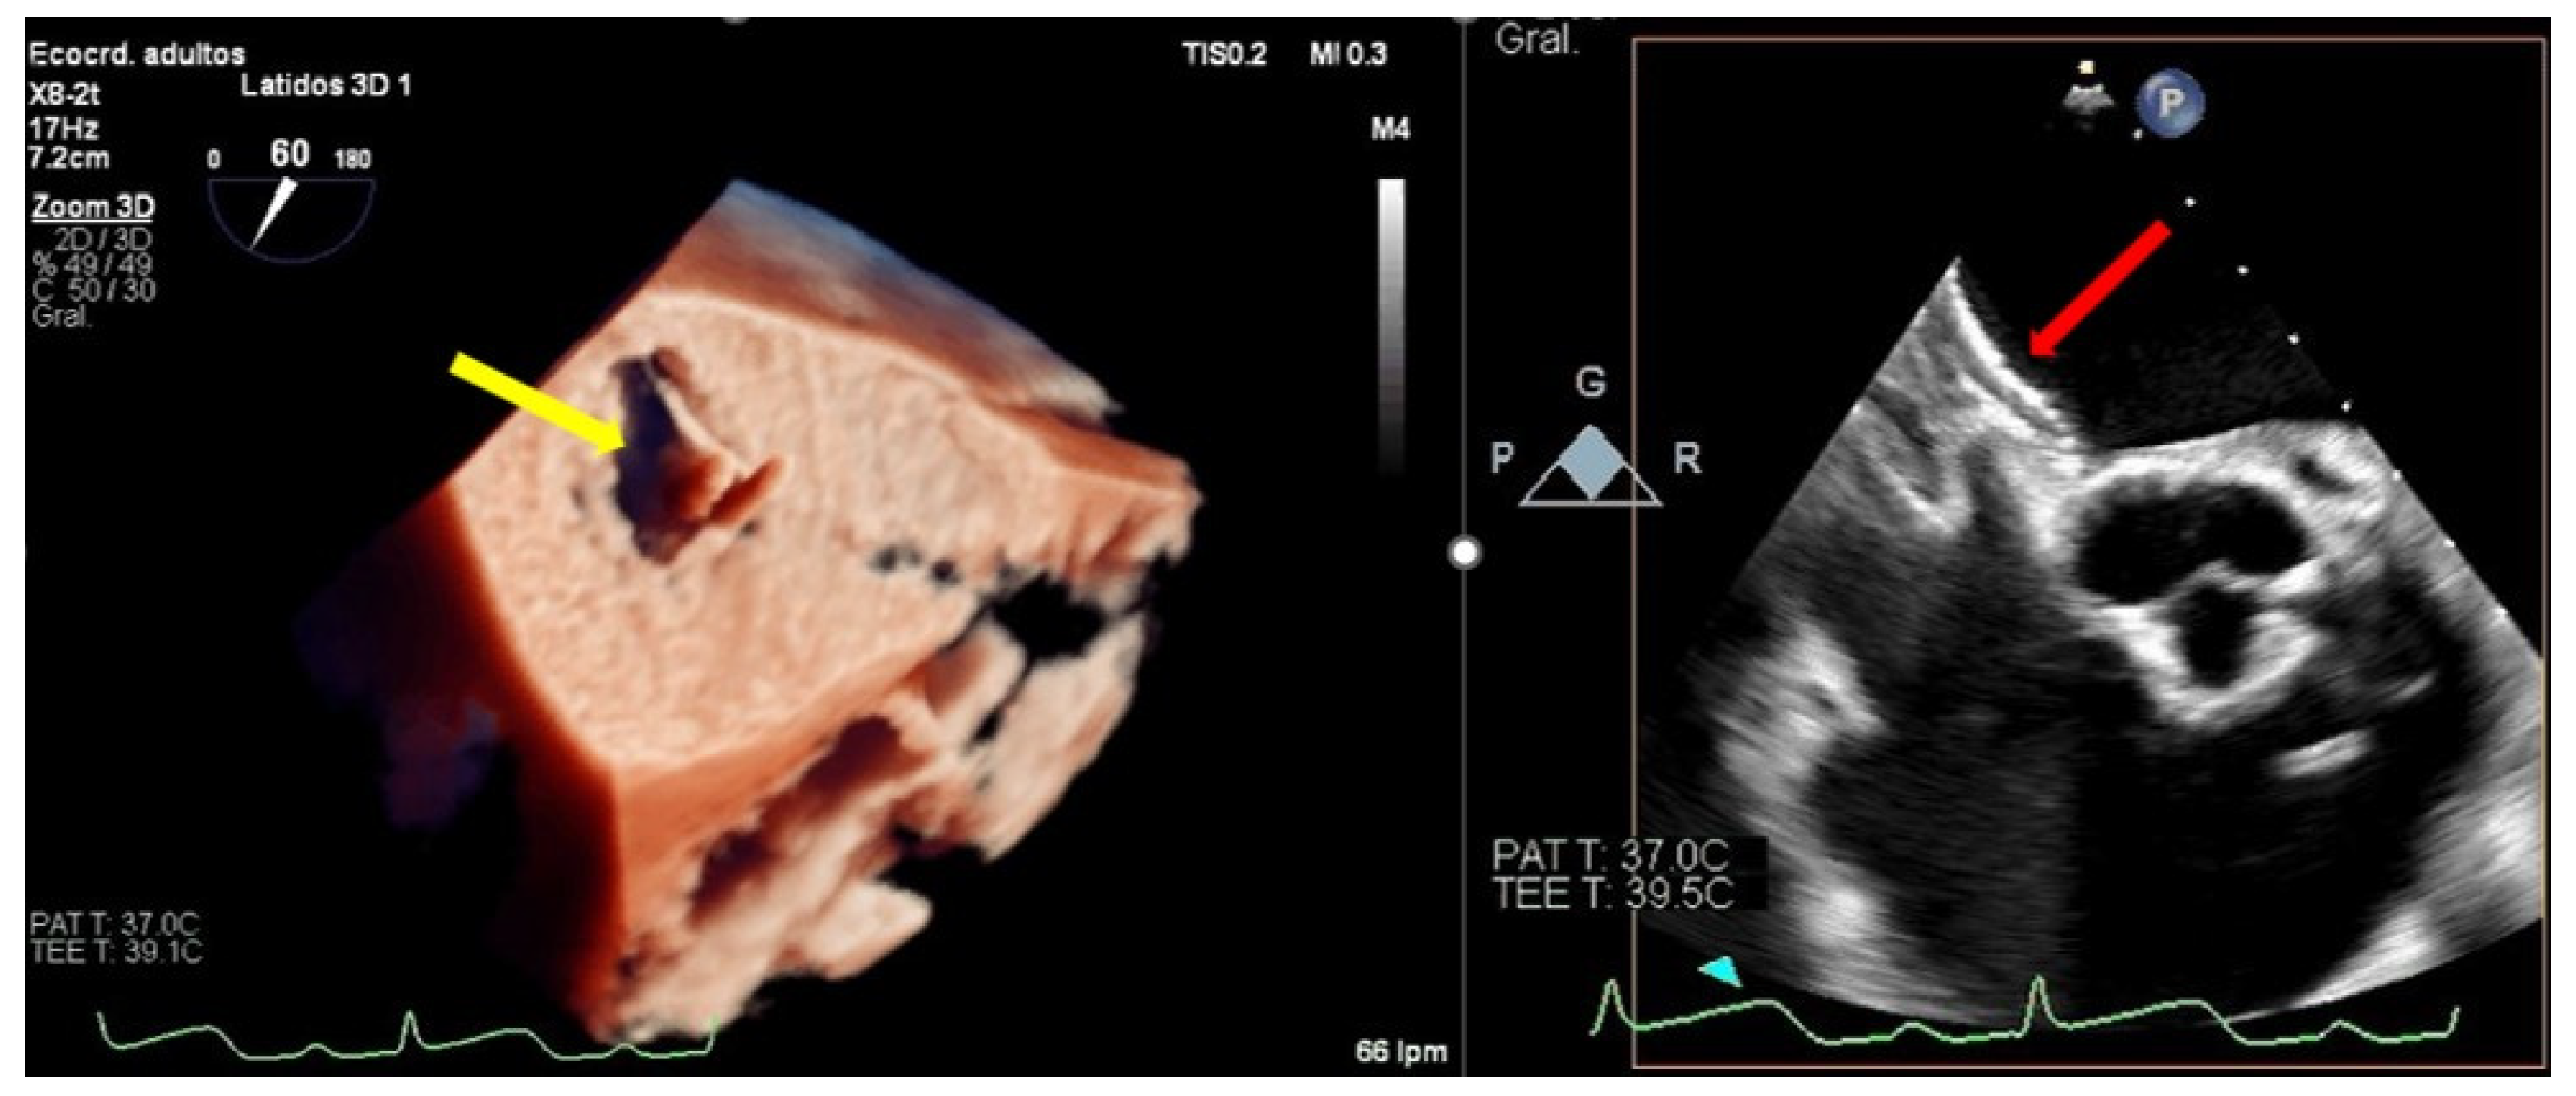

Figure 4.

Transesophageal echocardiogram during grasping. (Left) Two-dimensional transesophageal echocardiogram in the view of the left ventricular outflow tract, showing the tension of both leaflets and the measurement of the posterior leaflet introduced in the clip (red line delimited by plus sings). (Right) En-face 3D transesophageal echocardiogram view of the mitral valve with a clip between A2 and P2 with 2 symmetrical pyramids (red dotted lines).

Recently, the introduction of biplane images has facilitated the assessment of clip attachment due to the acquisition of simultaneous perpendicular views. Different authors have demonstrated that the additional use of 3D-TEE for the assessment of clip attachment may contribute to a reduced rate of subsequent clip complication [3]; therefore, the amount of both leaflets introduced into the clip must be assessed in a 3D enface view observing the amplitude of the inserted tissue and the formation of two pyramids whose vertex must be at least as wide as the clip (Figure 4). Checking a precise rotation of the device by 3D-TEE to avoid asymmetric grasping is another important step to avoid this complication, and, in addition, multiple leaflet grasps may lead to leaflet injury and should be avoided if possible.